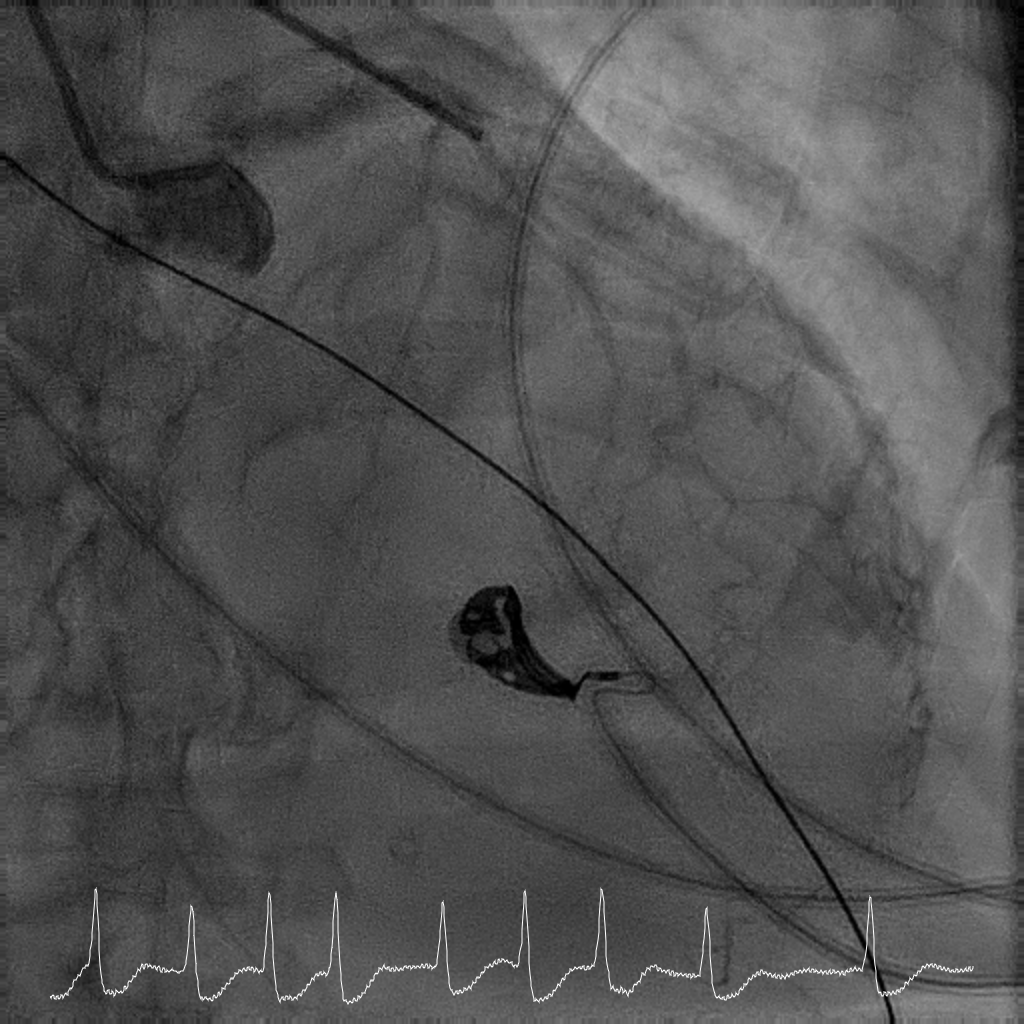

Rotational atherectomy with 1.5mm and then 2mm was performedfrom ostial LM to proximal LCx. Wiring of the LAD was only successful till midLAD with a separate distal LAD occlusion. LAD lesion was balloon uncrossableand half-way rotational atherectomy with 1.5mm burr. The distal LAD CTO wasthen crossed and balloon angioplasty undertaken. There was diffuse LAD disease, and the plan was then for ahybrid strategy. PCI to LM bifurcation was secured using the DK crushtechnique. 3.5x23mm Xience Sierra was placed in the LCx, 3.5x16mm Megatron inLM to proximal LAD followed by drug coated balloon angioplasty for the rest ofthe LAD with 2x40mm, 2.5x40mm, and 3x25mm balloon. She recovered well after her intervention and is infunctional New York Heart Association Class I, Canadian Cardiovascular Society Angina Grade 0. An elective angiogram was performed 6 months after indexprocedure to re-assess the results. This showed widely patient stents acrossthe LM-LAD-LCX, and excellent DCB results across the proximal to distal LAD andimprovement of her left ventricular ejection fraction.

This case illustrates the feasibility of a hybridrevascularisation strategy combining two-burr rotational atherectomy, left mainbifurcation stenting with DK crush, and downstream drug-coated balloonangioplasty in a patient with prohibitive surgical risk. Careful lesionpreparation and strategic device selection resulted in sustained long-termvessel patency and recovery of ventricular function in a patient with extreme-riskanatomy.